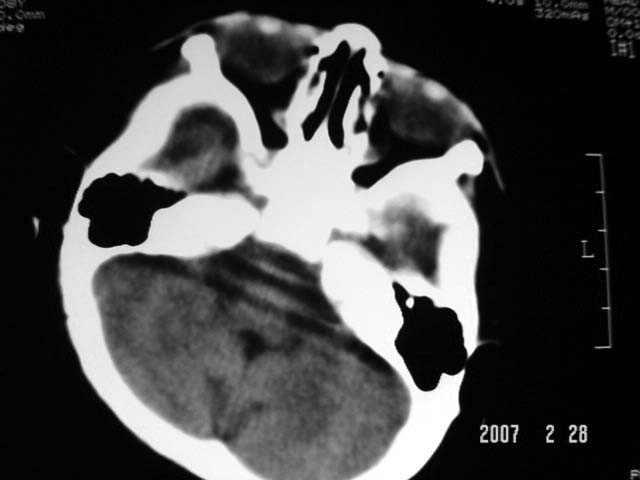

标题: PED0015:男,8M,发现不会坐立及神情异常,前囟已闭,双眼斜视,

脑回较深,白质范围小,灰白质比例失调。余未见明显异常。

考虑:脑白质发育不良,必要时请做mri进一步检查。